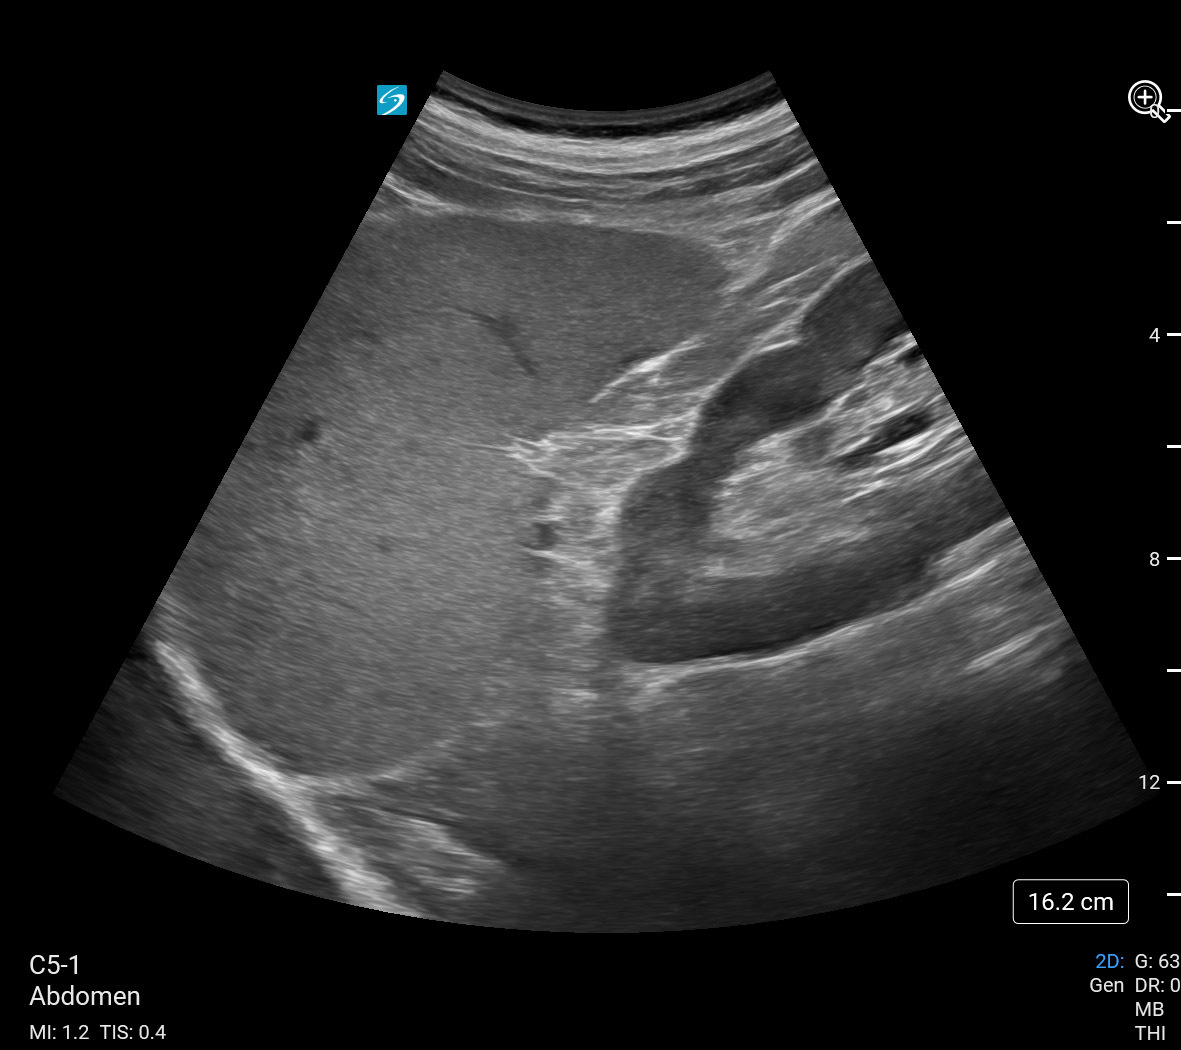

eFAST Left Upper Quadrant (LUQ) View (Sonosite PX C5-1) Image